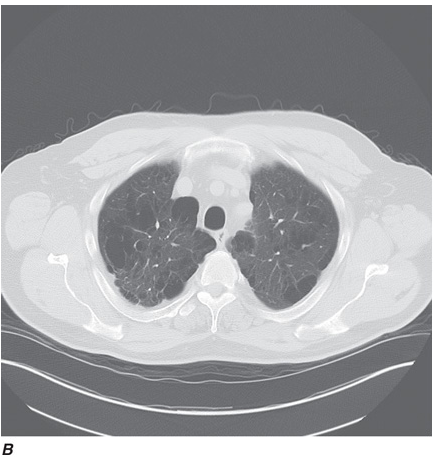

Computed tomography (CT) offers several advantages over routine chest radiography (Figs. C-1A, B and C-2A, B). First, the use of cross-sectional images allows distinction between densities that would be superimposed on plain radiographs. Second, CT is far better than routine radiographic studies at characterizing tissue density, distinguishing subtle density differences between adjacent structures, and providing accurate size assessment of lesions.

CT is particularly valuable in assessing hilar and mediastinal disease (which is often poorly characterized by plain radiography), in identifying and characterizing disease adjacent to the chest wall or spine (including pleural disease), and in identifying areas of fat density or calcification in pulmonary nodules (Figs. C-2A, B). Its utility in the assessment of mediastinal disease has made CT an important tool in the staging of lung cancer, as an assessment of tumor involvement of mediastinal lymph nodes is critical to proper staging. With the additional use of contrast material, CT also makes it possible to distinguish vascular from nonvascular structures, which is particularly important in distinguishing lymph nodes and masses from vascular structures primarily in the mediastinum, and vascular disorders such as pulmonary embolism.